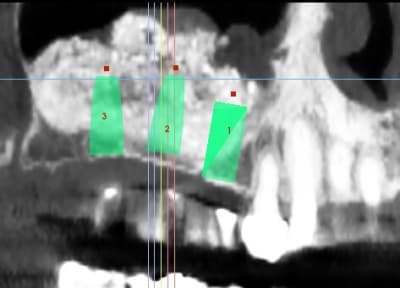

patiente ayant été implantée il y a 12 jours et toujours mal

le sinus lift a été pratiqué il y a 8 mois

j'avais repéré une perf, bien apparente, que j'ai protégée avec une Biogide

j'ai appris à mes dépens qu'un train peut en cacher un autre, savoir

une autre perf plus post, et donc quand je me suis rendu compte que le BM passait dans la deuxième perf,

j'ai interrompu la chir, ce qui explique la présence de lacunes

les implants ont été posés sans problème, et le BM était bien dense

ce qui m'ennuie ce sont les douleurs 12 jours après l'implantation